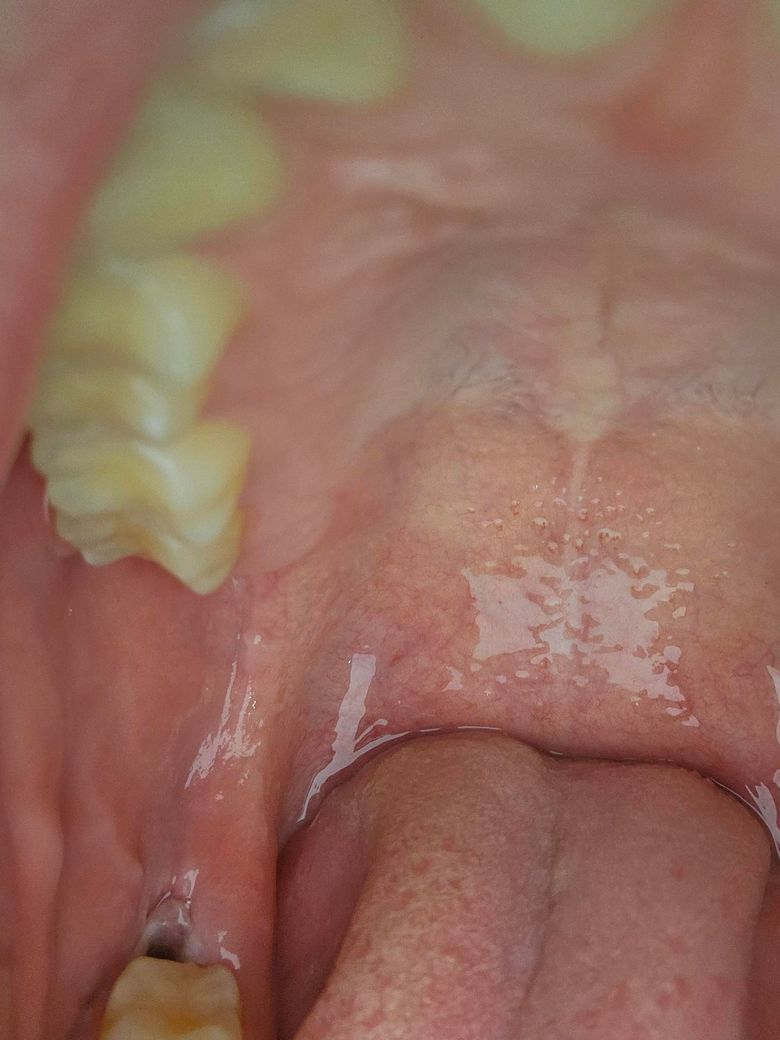

사랑니 발치 3일차입니다. 상태 한번 확인해주실 수 있을까요?

사진에 보시면 왼쪽 아래 수펑매복으로 있던 사랑니 저번주 토요일에 뽑았습니다. 통증같은건 없는데 제가 괜찮다보니까 햄버거에 파스타에 이런걸 먹고 다녔거든요. 근데 드라이소켓인지 뭔지 걱정되서 한번 질문해봅니다. 목요일날 ot가 있어서 아프면 안되거든요 ㅠㅠ 정상적인 치유 과정일까요?

정상적인 치유 과정으로 보입니다. 일반적으로는 자극적이고 맵고 짠 음식은 피하는 것이 맞으나 드셨을 때 큰 불편감이 없다면 드셔도 크게 상관은 없습니다. 드라이소켓은 2~3일째 갑자기 엄청난 통증이 오는 것이며 지금 상태에서 별다른 불편감이 없다면 걱정하지 않으셔도 됩니다.

아직까진 사진상 발치 부위에 어떤 문제점이나 특이소견은 관찰되지 않습니다

사진 상으로는 발치부위 양호한 치유 보이는 것으로 생각됩니다. 아직은 발치 후 며칠 안지난 상태이기때문에 조심히 생활하셔야하며 드라이소켓일 경우 극심한 통증 보이기 때문에 드라이소켓은 아닙니다.